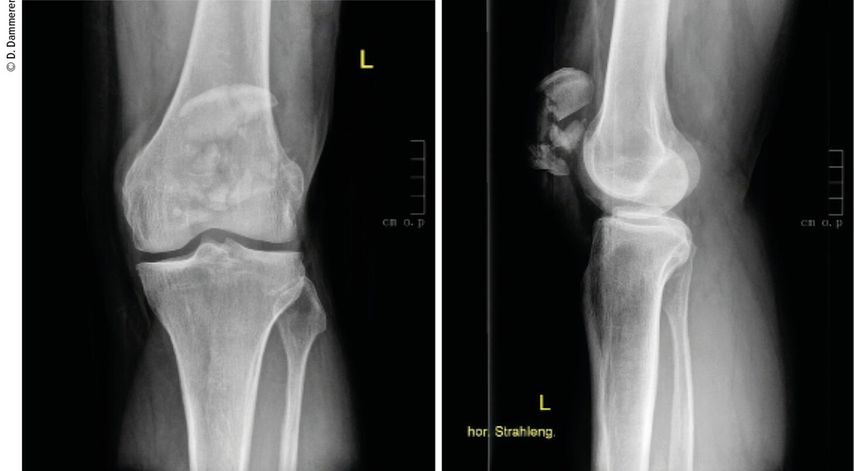

Abb. 1: Eine komplexe Mehrfragmentfraktur der Patella ergibt die Indikation zur operativen Versorgung